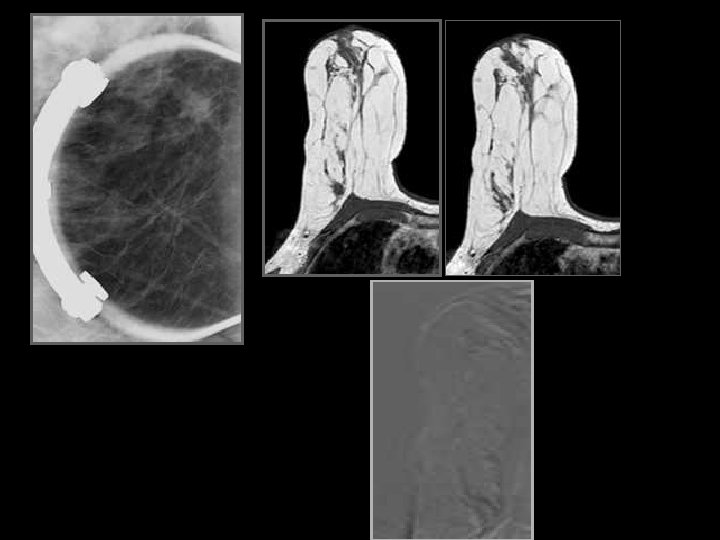

Injection - soustraction

Boetes 2004 • IRM : meilleure estimation en taille Breast Cancer Res Treat. 2004 Mx Radiologue 1 Echographie Mx Radiologue 2 IRM